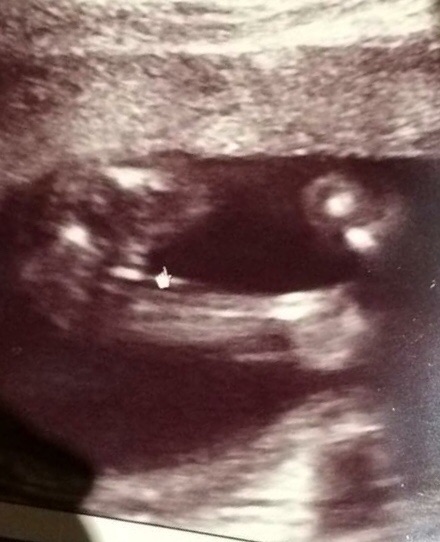

Is 18 weeks too soon to fond out gender? I've been seeing a lot of post about people being told girl and later boy. Does it look like my baby potty can change to boy parts? Sorry I'm a FTM and worried because I've already told everyone I'm having a girl. Thank you

To 2nd @mrskblack11, 18 weeks is to early to find out the GENDER of your future child. However, the 20 weeks and after mark is when most doctors/pregnancy books suggest to get your anatomy scan for the most accurate readings of the SEX of your child. A search of this topic on this board can help you identify the difference.